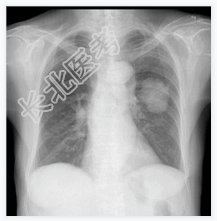

- [材料题] 患者,女性,83岁,低热一个多月,伴乏力、纳差、咳嗽,曾咯血丝痰。查体:体温,37.8℃;双肺呼吸音粗,未闻及明确干湿性啰音。心脏体查无异常。行胸部平片检查。

- 简答题1、请问该病例诊断是什么?

- 简答题2、请问诊断依据是什么?

- 简答题3、鉴别诊断有哪些?